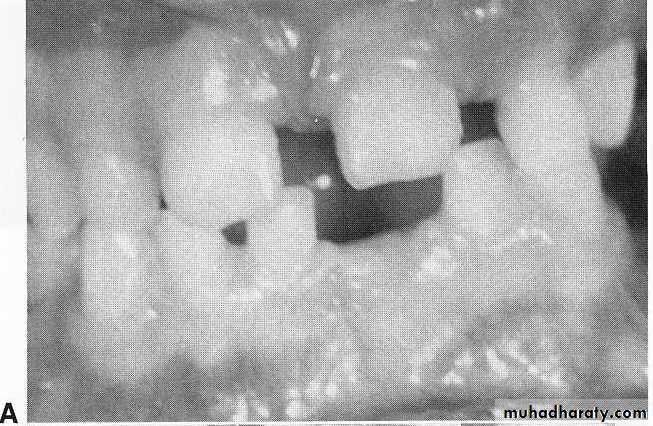

3. PREPUBERTAL PERIODONTITIS

LOCALIZED FORM:Localized prepubertal periodontitis (LPP) is localized attachment loss and alveolar bone loss only in the primary dentition in an otherwise healthy child.

appears to arise around or before 4 years of age

the bone loss is usually seen on radiographs around the primary molars and/or incisors

Affected sites may present with:

Abnormal probing depths with minor gingival inflammation,

rapid bone loss, and,

minimal to varying amounts of plaque.

Abnormalities in host defenses (e.g., leukocyte chemotaxis), extensive proximal caries facilitating plaque retention and bone loss, and a family history of periodontitis have been associated with LPP in children

Micro-organisms predominating in the gingival pockets include Actinobacillus actinomycetemcomitans (Aa), Porphyromonas (Bacteroides) gingivalis.

A, Prepubertal periodontitis in a 41/2-year-old girl. Loosening, migration, and spontaneous loss of the primary teeth occurred.

B, A generalized loss of alveolar bone can be

seen in the radiographs.